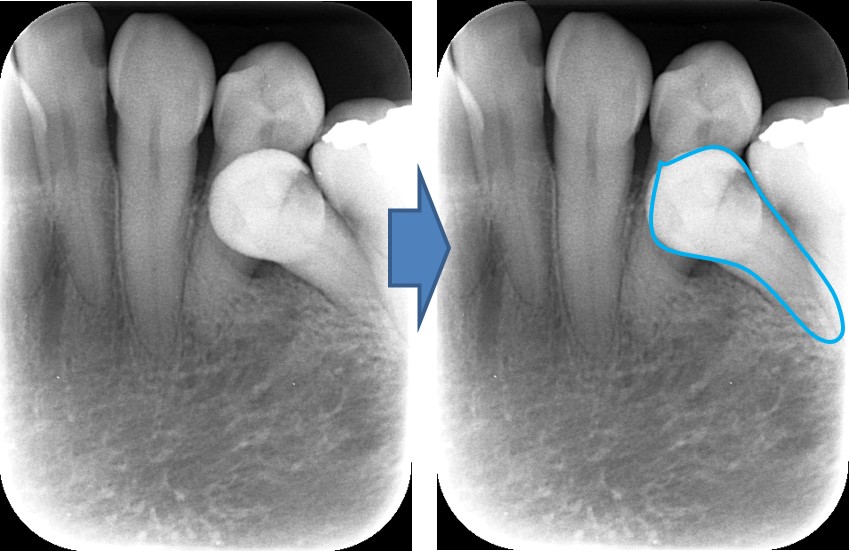

← 195.歯の移植